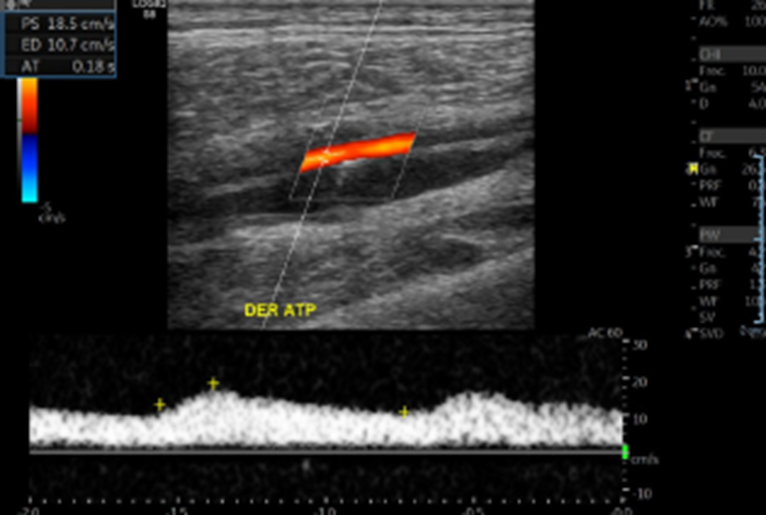

• Curvas arteriales de EEII DER con pérdida de su componente trifásico. Se observan con disminución de VPS habituales y con aumento de su TA.

• Oclusión de AFS distal. Existe una colateral proximal que reconstituye flujo a nivel de Arteria poplítea. Curvas posteriores con tardus parvus.

• ATA y A Pedia con leves peak de VPS.

Hallazgos: Con transductor lineal de alta frecuencia se explora el territorio arterial de la extremidad inferior derecha incluidas las arterias femorales común, femoral superficial, poplítea, tibiales anterior y posterior, peronea y pedia. Placas de ateroma calcificadas en todo territorio arterial de la extremidad inferior, con extensa placa a nivel de la arteria femoral común y profunda generando estenosis de aproximadamente 75% (aumento de velocidad peak sistólico desde 50 cm/s hasta 244 cm/s), con curvas espectrales de morfología parvus tardus en arteria femoral profunda distal a la estenosis. Oclusión completa de la arteria femoral superficial distal, con desarrollo de colaterales que permiten flujo hacia la arteria poplítea. Disminución de velocidad peak sistólico del resto de los vasos de la extremidad inferior, con curvas espectrales de morfología monofásica y parvus tardus. Incidentalmente, se observa aneurisma fusiforme de la aorta abdominal a nivel infrarrenal, en una extensión aproximada de 11.7 cm, con diámetro transverso de 7. 2 cm y anteroposterior de 6.9 cm, con prominente trombo mural que determinan gran disminución del lumen arterial.

Ateromatosis cálcica difusa de la extremidad inferior con extensa placa a nivel de la arteria femoral común y profunda generando estenosis de aproximadamente 75%. Oclusión completa de la arteria femoral superficial distal, con desarrollo de colaterales que permiten flujo hacia la arteria poplítea. Marcada insuficiencia arterial del resto de los vasos de la extremidad inferior. Voluminoso aneurisma fusiforme de la aorta abdominal a nivel infrarrenal, con prominente trombo mural que determinan gran disminución del lumen arterial. Es indispensable evaluación clínica y complementar estudio con AngioTAC de abdomen y pelvis y extremidades inferiores.